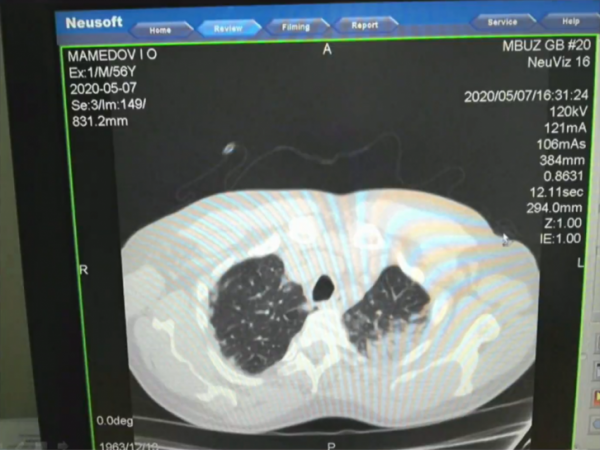

Глава Минздрава Ростовской области Татьяна Быковская во время заседания оперштаба показала снимки органов легких у людей с подтвержденным коронавирусом. На слайдах видно, как инфекция поражает легочную ткань, оставляя матовые помутнения.

— Всё, что темное, — это ткань легкого, а светлое — так называемое матовое стекло. Это показатель того, что наступает необратимый процесс. Легкие наполняются кровью, и дышать пациент самостоятельно не может, — объяснила Быковская.

Из-за того, что такие поражения легких на снимках выглядят помутневшими, врачи и ученые называют его «эффектом матового стекла». Оно проявляется даже у тех, кто переболел коронавирусом без симптомов. Ранее ученые выяснили, что примерно две трети заболевших переносят коронавирус без видимых симптомов. При этом у половины из них есть пневмония, которую пациенты не могут заметить самостоятельно.

Темное — это ткань легкого, светлые пятна — поражения

Фото: оперштаб по коронавирусу Ростовской области